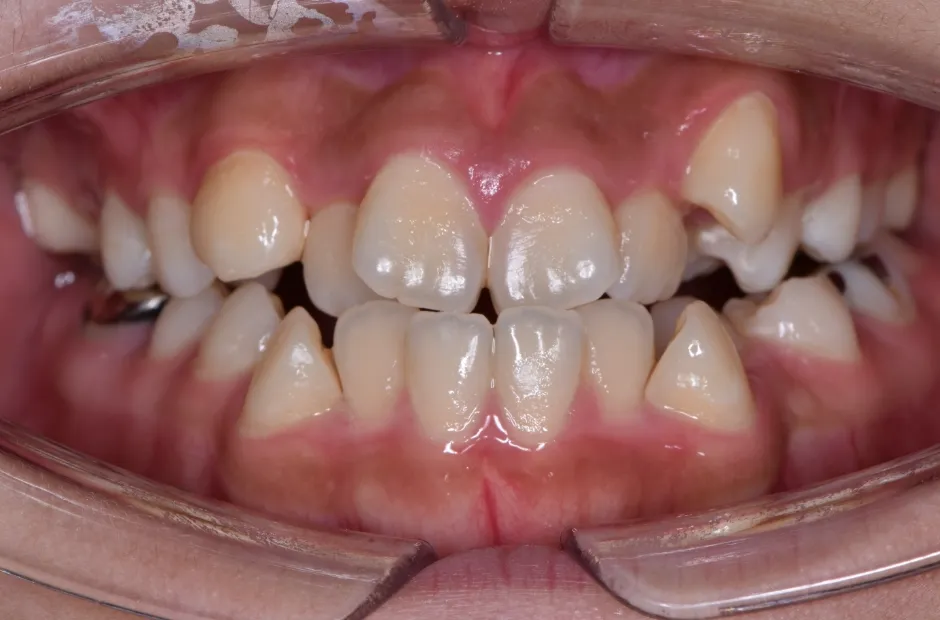

治療症例

ブラケット矯正

前歯部反対咬合

| 診断名・主訴 | 前歯部反対咬合 |

|---|---|

| 年齢・性別 | 14歳・男性 |

| 治療期間・回数 | 1年2か月 |

| 治療に用いた主な装置 | ブラケット矯正 |

| 抜歯部位 | なし |

| 治療費 | 60万円(税抜) |

| リスク・副作用 | 装置による違和感・疼痛・歯肉退縮・歯根吸収・虫歯のリスクなど |

治療前